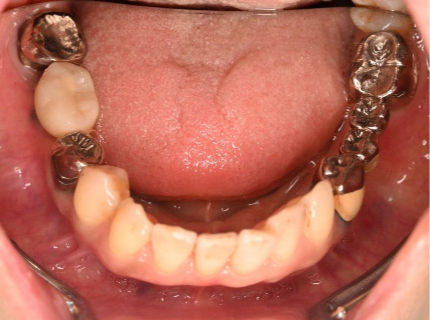

男性 Kさん 60代 (インプラント)

主訴

下の左右歯がないところに歯を入れたい。

治療内容

左右それぞれ3本歯がないところに2本ずつインプラントを埋入しました。

所感

上と下の歯の咬合接触がないすれ違い咬合です。上下義歯で対応するには最も難しいタイプの欠損状況です。治療開始前は、上下部分入れ歯が入っていましたが、入れ歯の安定が悪く、あちこちの歯茎に入れ歯が当たって痛く、満足に噛める状態ではありませんでした。上顎は、残ってる歯を活用するマグネット式総義歯を、下顎はインプラントを提案しました。上顎は、現在残っている歯の根管治療中です。上顎にマグネット式総義歯がはいれば、何でも食べられるようになります。

インプラント4本:¥363,000×4本=¥1,452,000(税込)

ポンティック2本:¥115,500×2本=¥231,000(税込)

合計:¥1,683,000(税込)

Before

▼初診時に使用していた部分入れ歯を装着したところ

▼インプラント埋入前

After

▼インプラント埋入後